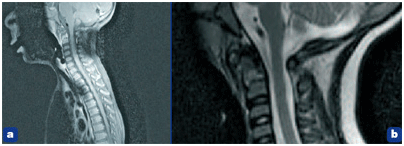

La scintigraphie osseuse montre une hyperfixation tardive se projetant au niveau des vertèbres cervicales C1 – C2 (figure 2), mais ne permet pas de trancher entre l’hypothèse traumatique et la spondylodiscite. C’est l’IRM cervicale qui apporte le diagnostic de certitude (figure 3), confirmant un aspect de spondylodiscite cervicale C1–C2, sans épidurite ni signe d’atteinte médullaire.

Figure 3. IRM cervical en coupe sagittale T1 avec injection (a) et en T2 avec agrandissement (b). On note un hyposignal de l’odontoïde en T1 avec rehaussement périphérique lié à l’injection de gadolinium ainsi qu’un léger hyper signal T2.